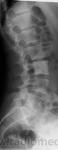

Миелосклероз (миелофиброз) тоже из песни слов не викинуть, но в авторском случае один позвонок "бластный"

ИЗМЕНЕНИЯ КОСТЕЙ ПРИ ЗАБОЛЕВАНИЯХ РЕТИКУЛО - ЭИДОТЕЛИАЛЬНОЙ СИСТЕМЫ И ОРГАНОВ КРОВОТВОРЕНИЯ

Так называемая остеосклеротическая анемия (миелофиброз, миелосклероз). Та же больная. Деталь рентгенограммы позвоночника. Мраморность III—V поясничных позвонков.

Заболевание кроветворной системы, характеризующееся анемией, лейкопенией со сдвигом влево, гепотоспленомегалией, расстройствами функции гипофиза и нервной системы, изменениями в костях.

Рентгенологическая картина

В костях таза, позвоночнике, ребрах, в проксимальных отделах трубчатых костей на фоне грубопетлистой структуры определяются участки разрежения и очаги склероза; костно-мозговой канал сужен. Иногда наблюдается равномерный склероз ("мраморность"), особенно в костях таза и в позвоночнике.